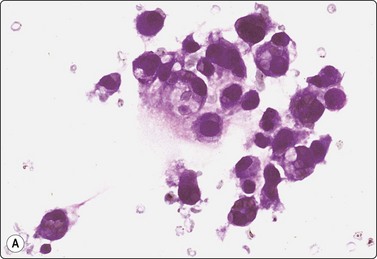

image image

Fig. 12.31 Transitional cell carcinoma

(A) Mixed population of non-neoplastic tubular epithelium and malignant cells with dense cytoplasm and eccentric nuclei (MGG, HP); (B) Corresponding tissue section; carcinoma cells infiltrating between normal renal structures (H&E, IP).

Criteria for diagnosis

High cellularity; cells single and in syncytial clusters; rarely papillary structures,

Large pleomorphic nuclei; variable hyperchromasia; coarse chromatin,

Eccentric nuclei within a dense cytoplasm,

Prominent nucleoli,

Cercariform cells often present,

Most tumors are CK7+ and CK20+.

Transitional cell carcinoma (TCC) developing from the epithelial lining of the renal pelvis involves the parenchyma by invasion and the malignant cells may therefore be intimately mixed with non-neoplastic tubular epithelial cells in FNB smears (Fig. 12.29). Most of the tumors subjected to FNB are solid and high grade, and true papillary structures are not often found. A tendency to squamous differentiation is not uncommon, some tumors have a spindle cell pattern and some are highly anaplastic and cannot easily be identified as of transitional cell origin. So-called ‘cercariform’ cells, which have long unipolar cytoplasmic processes with a thickening at the tail, are regarded as a clue to the recognition of TCC in smears.108,109

The distinction between RCC and TCC is not always easy. TCC sometimes has a clear cell appearance in tissue sections and correspondingly a pale vacuolated cytoplasm in smears. This is usually a focal phenomenon; the nuclear:cytoplasmic ratio is still relatively high and the nuclei are hyperchromatic with a coarse, irregular chromatin. Tumor cells are positive for CK7, usually also for CK20, high molecular weight cytokeratin and thrombomodulin, negative for RCC antigen and CD10.